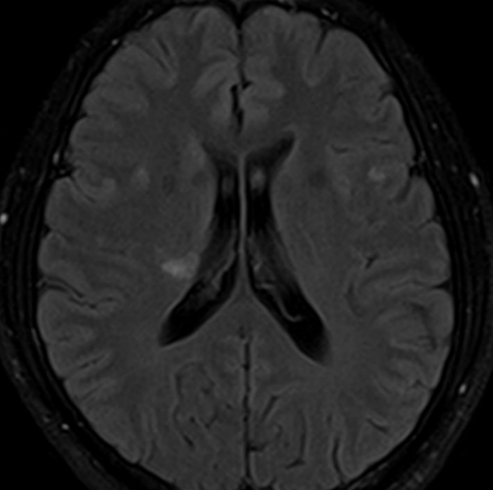

=>lacune 의심 (Clumsy hand syndrome)

==> Rt M1 stenosis

==> 3년이 지난 현재 증상은 지속되지만, 악화는 없으며, TCD검사에서 MCA의 협착이 진행하지 않고 고정되어 있음

O) MRI 에서 우측 BG에 쐐기모양의 old infarction 병변 보임. CTA에서 Rt M1 보다 원위부 혈관이 보이지 않음

2012년경 좌상지 clumsy 발병하여 경대병원 응급실에서 치료받은 후, 경대병원서 지금까지 F/U 중.